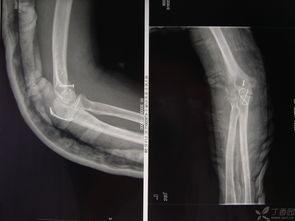

3. 形状改变:上臂的形状可能会发生改变,比如变短或弯曲。

4. 功能受限:上臂的活动能力会受到影响,比如抬不起来。